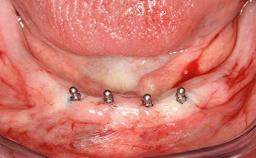

Mandibular Overdenture Supported by a CAD/CAM-milled Bar with Long Distal Extensions on Two Conventionally Loaded Implants

An 87-year-old man was referred to our Division of Gerodontology and Removable Prosthodontics at the University Clinics of Dental Medicine, Geneva, Switzerland for dental implant therapy. He was retired and led a very active social life, keeping himself busy in the company of his many grandchildren and with frequent travels to Italy. The patient’s past medical and drug histories revealed that he suffered from angina, asthma, and arthritis of the knee. He was allergic to penicillin. His regular prescription medications included anti-anginal and antiasthmatic drugs, along with occasional non-steroidal anti- inflammatory drugs for joint pain. Otherwise, he was a healthy patient who occasionally consumed alcohol on social occasions and did not smoke. A detailed dental history revealed that he had lost his teeth to chronic adult periodontal disease and had had an edentulous maxilla for over 20 years.